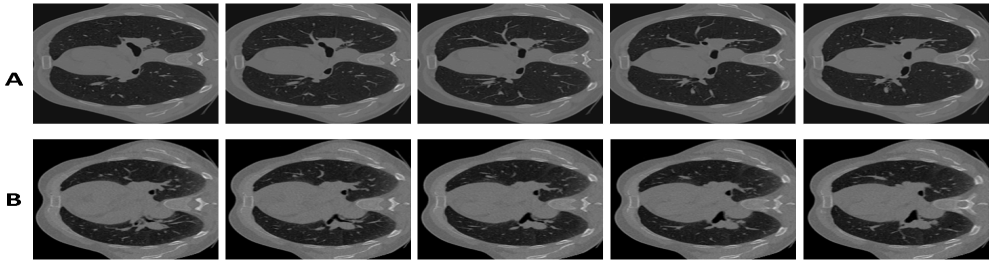

Refer to caption

Figure 1: Panel A presents representative central axial slices (102 to 106) from the fixed images of Case 1 in the DIRLab dataset, whereas Panel B illustrates the corresponding slices from the moving images of the same case.